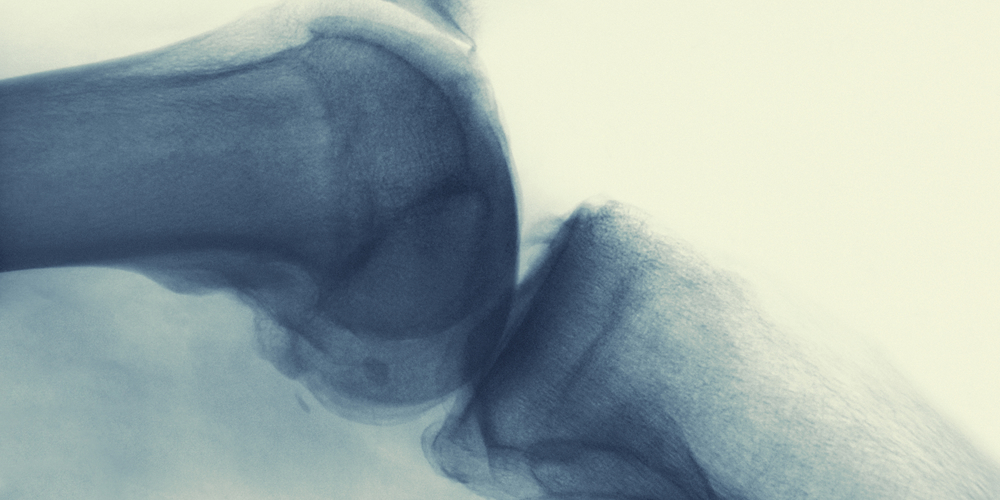

Kathleen Derwin Lab

The Derwin lab identifies factors which influence healing and outcomes following rotator cuff repair.